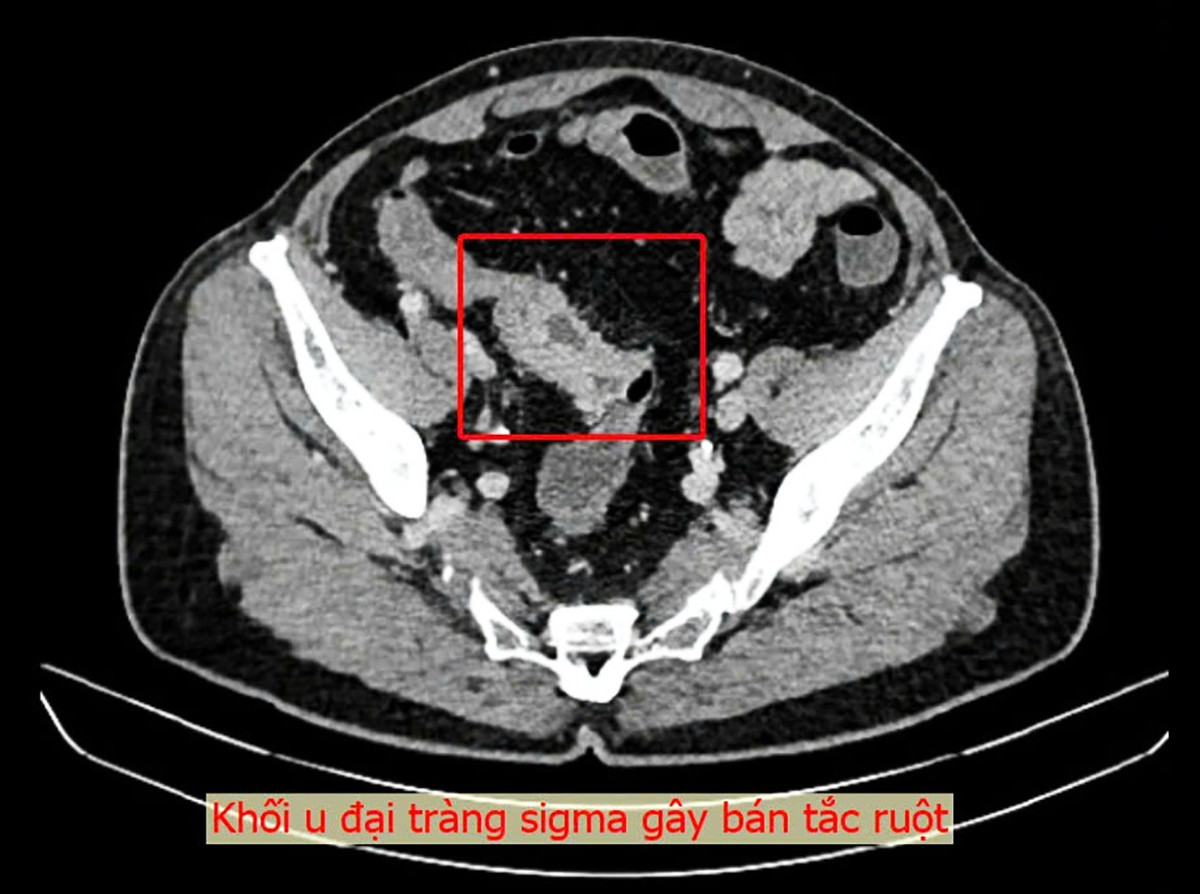

Một ca phẫu thuật nội soi thành công đã được thực hiện tại Bệnh viện Đa khoa Thủ Đức để điều trị cho nam bệnh nhân Việt kiều 73 tuổi bị bán tắc ruột do khối u đại tràng sigma.

Trong thời gian về Việt Nam, bệnh nhân đã đến khám tại Bệnh viện Đa khoa Thủ Đức. Qua nội soi đại tràng, các bác sĩ phát hiện một khối u lớn tại vị trí sigma-trực tràng, chiếm trọn lòng trực tràng, với đặc điểm mô bở và dễ chảy máu. Sau khi đánh giá toàn diện và xét nghiệm cần thiết, ê-kíp bác sĩ xác định đây là khối u ác tính và cần phẫu thuật gấp.